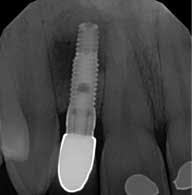

Upon examination, the No. 10 implant had a healing abutment placed and was noted to have circumferential loss of 3 mm to 4 mm of hard and soft tissue. This loss of tissue was significant enough that the collar of the implant fixture was now at the facial tissue margin. Also, tooth No. 9 had 5 mm of clinical attachment loss, and the tooth had been recently devitalized. A soft tissue lesion was also noted in the unattached tissue buccal to the apex of the No. 7 implant. The lesion appeared to be unproductive. A radiograph showed a large radiolucency around the apex of the No. 7 implant. The patient was referred to the periodontist to evaluate Nos. 9 and 10 for possible tissue graft and to find the origin of the lesion apical to the No. 7 implant.